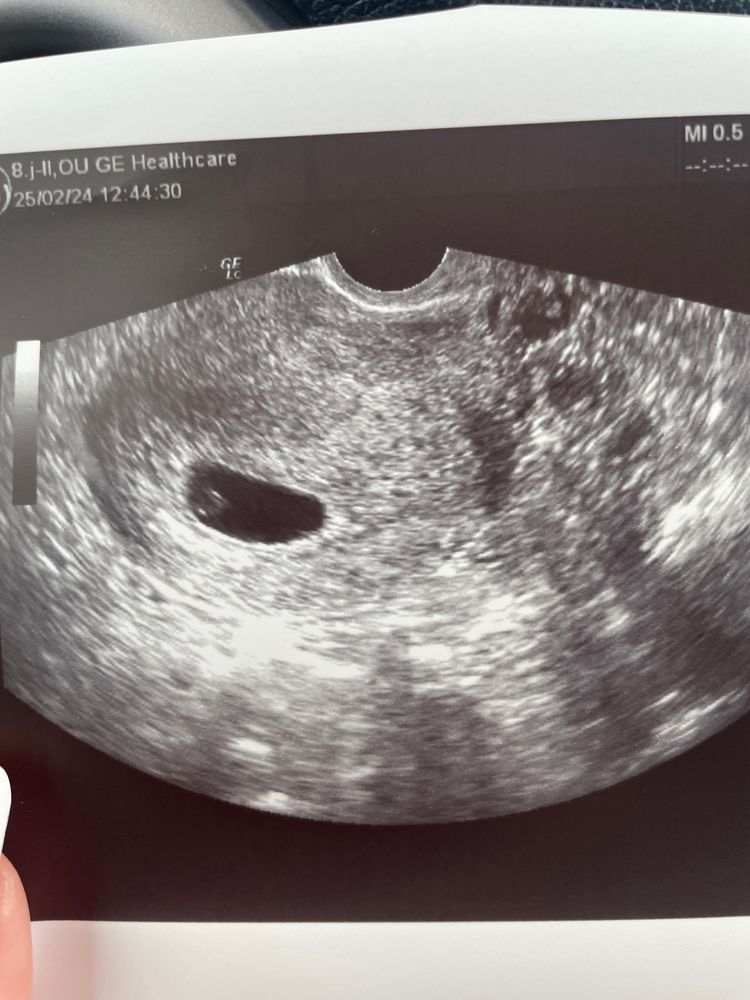

УЗИ 5 недель

ПЯ: 20,8 * 8,7мм

КТР: 1,4мм

ЖМ: 3,4мм

Сердебиение написали определяется😮💨 но пока не очень хорошо слышно, сказали придти повторно через 4 дня🙏🏻

по месячным срок 5,2

по УЗИ написали 5,1